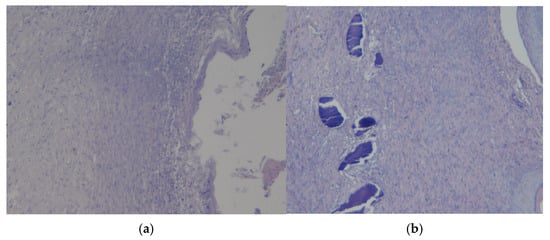

3.3. Results of Morphological Examination

3.4. Assessment of Microcirculation in the Healing Process of Burn Wounds